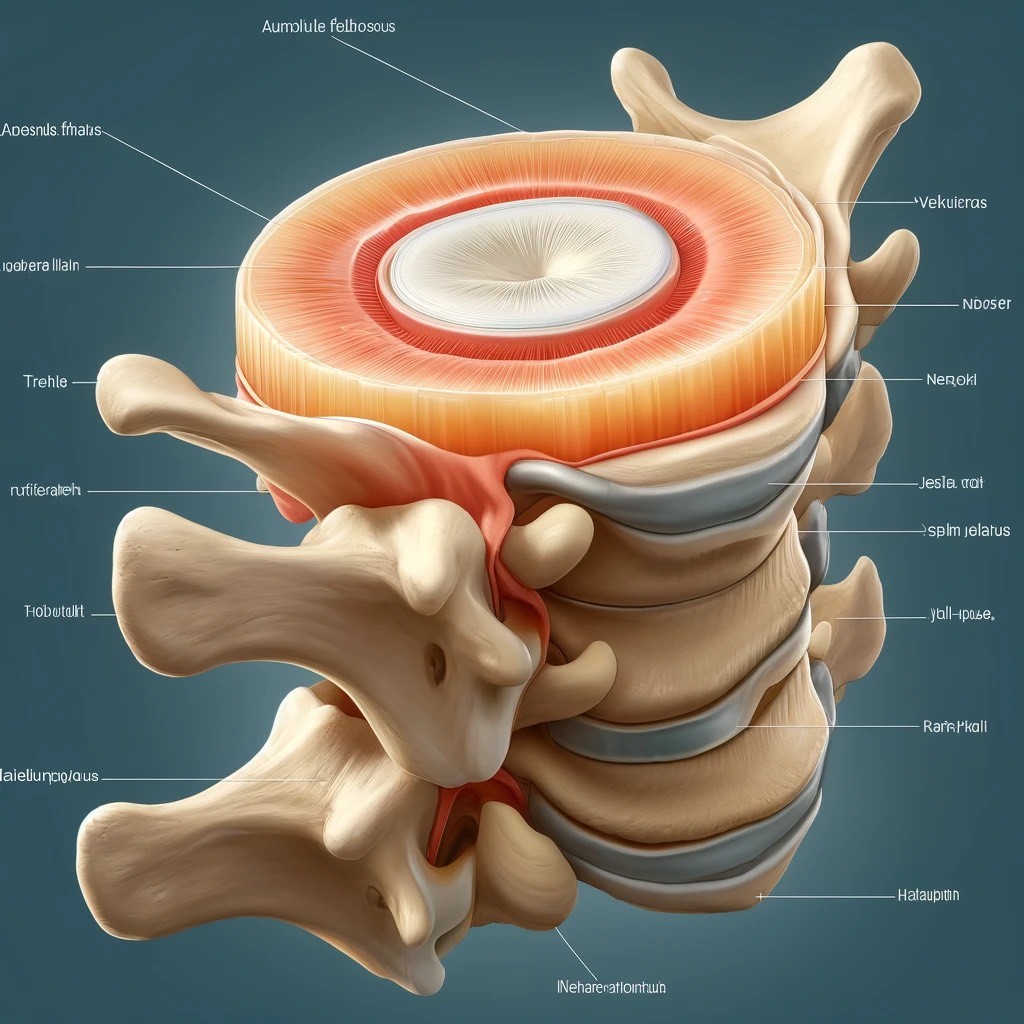

КТ-протрузии дисков: Визуализация и классификация